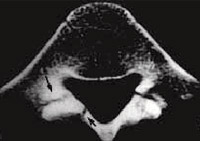

Fig. 4 - Tomografia axial computadorizada, nível do disco L4-L5 de surfista com 20 anos. Fratura do anel apofisário (seta) que acompanha hérnia discal central L4-L5.